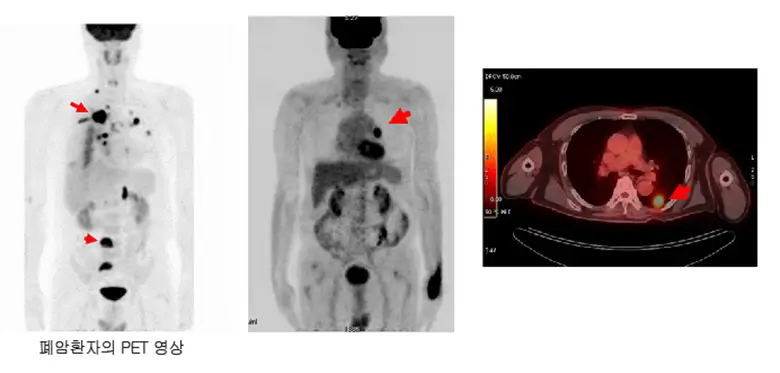

PET-CT

- PET-CT는 전신의 암 전이를 확인하는 데 사용되는 중요한 검사로, 포도당과 유사한 방사성 동위원소를 사용하여 대사 활동이 활발한 암세포를 찾아내고, 전이된 부위를 시각화합니다. 이를 통해 전체 암의 범위를 평가하고, 정확한 병기를 설정할 수 있습니다.